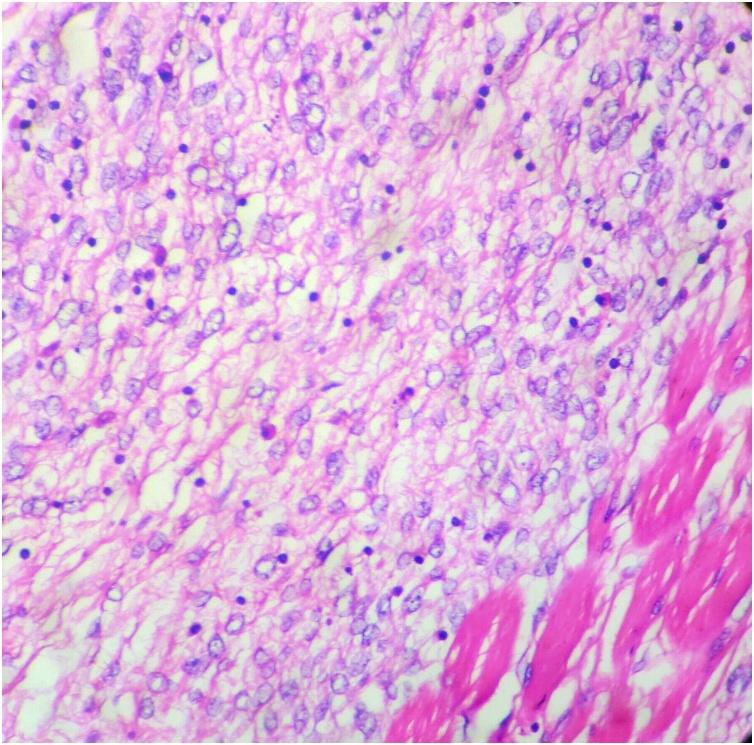

A 48 year old female presented initially with a localised swelling of 2 cms diameter in the front of the left elbow in 2007, which was excised. It recurred repeatedly and was excised. In the earlier presentations, the swellings were firm, mobile and not fixed to bone. In the last stage alone, bone fixity was identified. All the fourteen surgeries were performed by the primary author from 2007 to 2020, as the patient was particular. THE MAIN CLINICAL DIAGNOSES: had been neurofibroma and fibrosarcoma. There was no evidence of distant metastasis all these years. She did not respond to radiation or chemotherapy. Initially it was single, but later multiple. She had no clinical features of Neurofibromatosis 1 (NF1) or any family history. As the history progressed, the swellings became muscle deep and later encircled the radial nerve. The radial nerve was salvaged on three occasions. On the last three occasions, the tumour had to be shaved off from the humerus. The final amputation specimen showed a single tumour infiltrating the humerus and x-ray revealed bone destruction and tumour calcification. Final diagnosis was aided by immunohistochemistry (IHC) and cytogenetic study (FISH).

一名48岁女性于2007年首次就诊,左肘前部出现一个直径2厘米的局限性肿块,该肿块被切除。它反复复发并被切除。在早期表现中,肿块质地坚硬、可活动,未与骨骼固定。仅在最后阶段才发现与骨骼固定。从2007年到2020年,所有14次手术均由第一作者进行,因为患者比较挑剔。主要临床诊断曾为神经纤维瘤和纤维肉瘤。这些年来均无远处转移的证据。她对放疗或化疗均无反应。最初是单发,但后来变为多发。她没有神经纤维瘤病1型(NF1)的临床特征或任何家族史。随着病程进展,肿块深入肌肉,后来环绕桡神经。桡神经曾三次得以保留。在最后三次手术中,不得不从肱骨上刮除肿瘤。最终截肢标本显示单个肿瘤侵犯肱骨,X线显示骨质破坏和肿瘤钙化。免疫组织化学(IHC)和细胞遗传学研究(FISH)辅助做出了最终诊断。